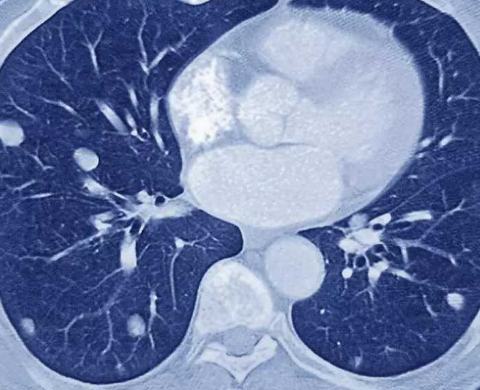

90%以上累及胸部,常侵犯双侧肺门淋巴结及肺。其临床表现多种多样,缺乏典型性,X线胸片及常规CT发现肺门增大,高分辨率CT能够更进一步了解纵隔淋巴结肿大以及肺内病变细节,可明确提示结节病诊断,结合临床及活组织检查,可大大提高诊断率。

肺部结节与肺结核病发的位置也大不相同。肺结节基本会生长在双侧肺门或者肺部的淋巴结处。很少会造成其他部位的病变,即使肺部结节增多,也只会出现在这附近。而肺结核由于是细菌感染造成的,会造成肺部黏膜受损,并且随着病情的发展,感染的面积就会越来越大,患者很可能由单侧肺结核演变称为双侧肺结核。